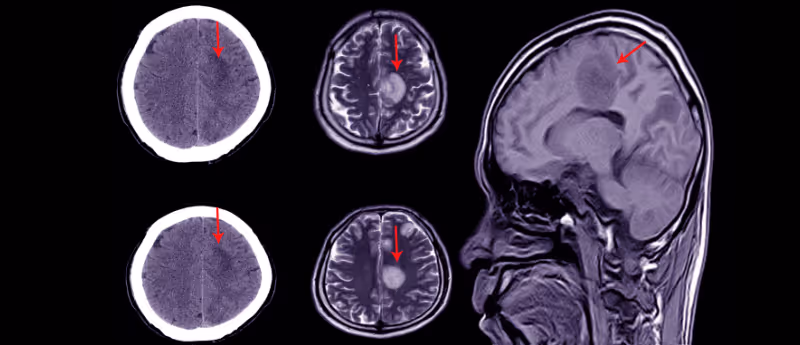

Unfortunately, most functional and structural brain injuries from concussions are difficult to detect with CT imaging scans unless they are severe. Consequently, it is difficult to accurately diagnose concussion and pick up on tiny structural alterations in the brain.

Utilizing machine learning to analyze hundreds of brain MRI scans of student athletes, the program was able to distinguish between the brains of 36 contact sport athletes (such as football) and the brains of 45 non-contact sport athletes (such as track and field). The program clearly associated repeated head trauma with miniscule structural brain differences in contact sport athletes who had not been diagnosed with concussion.

The machine learning model was trained with previous data from the MRI scans of almost 100 male athletes, from both contact and non-contact sports, who were not diagnosed with a concussion during the model training period. The researchers scored the most useful MRI metrics for detecting damage: mean diffusivity (how easily water can travel through the brain) and mean kurtosis (a marker for tissue heterogeneity that gives important microstructural information). This information was used to optimize the model and improve the concussion diagnosis accuracy.

“Our results highlight the power of artificial intelligence to help us see things that we could not see before, particularly ‘invisible injuries’ that do not show up on conventional MRI scans,” declared study lead author Junbo Chen, a doctoral candidate at NYU Tandon School of Engineering (NY, USA). “This method may provide an important diagnostic tool not only for concussion, but also for detecting the damage that stems from subtler and more frequent head impacts.”